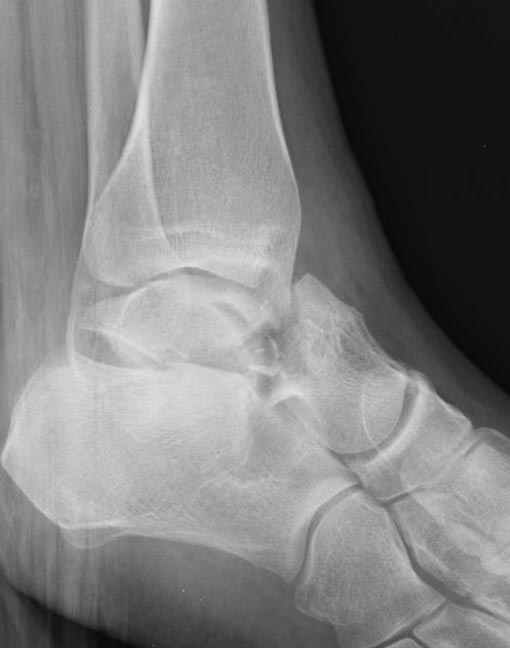

Вдогонку по поводу перелома таранной кости, больная 81, не страдает диабетом, перелом закрытый, в первый же день поступления ограничились временным наружным фиксатором (как на снимке).

Планировалась открытая фиксация после спадения отека, но больная пожелала лечиться по месту жительству в другом штате..

За пару недель насчитал 5 больных с переломом таранной кости, из них двое с двусторонним повреждением.

Из-за отека на стопе тактика лечения у всех была

одинаковая: временная наружная фиксация до спадения отека, при изолированных переломах они выписывались домой и через дней 7 госпитализировались на оперативное лечение.

Примеры на снимке...